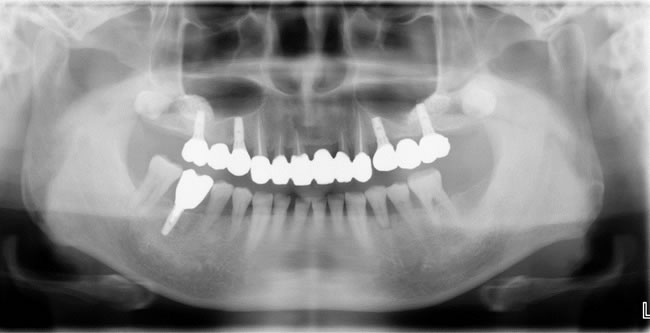

現在 メインテナンスに入り7年経過しています。

歯周病治療、サイナスリフト(骨造成)をしてインプラント治療をおこない、健康的な生活を維持でき、糖尿病も安定しています。

患者さんはインプラントによって奥歯がしっかり咬めるため、噛み応えのある高蛋白質の食べ物を美味しくいただけるそうです。